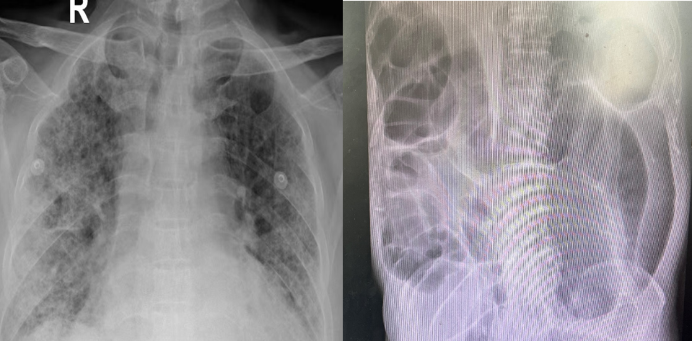

血气分析:pH 7.45,PaCO2 42 mmHg,PaO2 93 mmHg,FiO2 70%,P/F 133 mmHg,SaO2 98%复查胸片肺部感染,尤其右下肺实变影较前明显改善出现了新的问题——患者腹胀明显,腹部平片可见明显肠胀气(图4)

4  复查胸部X线片和腹部平片

2)胃肠危机的破局时刻

针对患者的腹胀症状,我们采取了一系列综合干预措施:首先,进行常规腹内压监测以动态评估病情;饮食上采用空肠喂养,并加用胃肠动力药物促进胃肠蠕动;同时,每日为患者进行腹部按摩及灌肠处理,以改善肠道功能。此外,通过调整呼吸机参数、减少镇痛镇静药物用量,降低对胃肠功能的影响;还联合中医治疗手段,包括中药外敷、针灸及中药内服,协同缓解腹胀。经上述处理后,复查腹部平片显示,患者因腹胀导致的肠胀气情况已明显好转(图5)

5  复查腹部平片